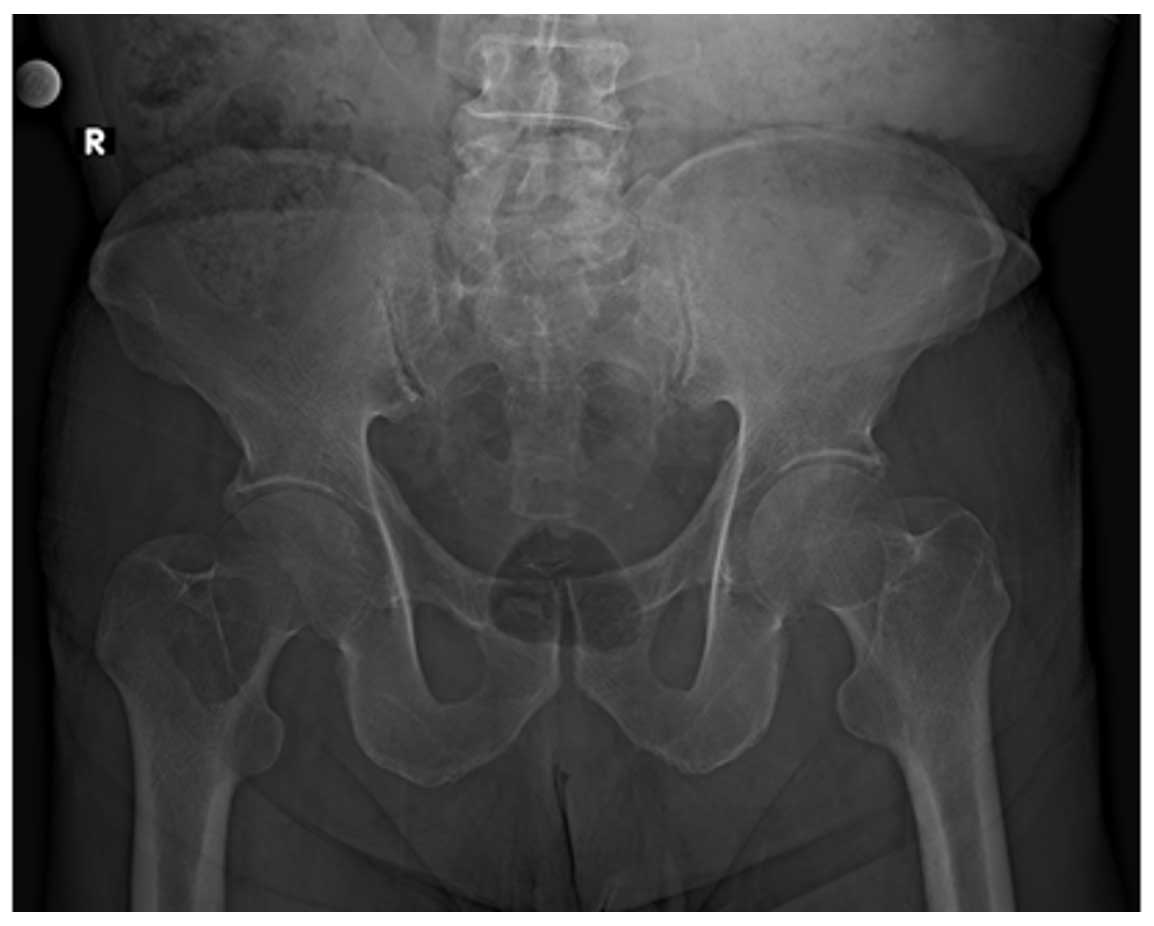

Ameliyat Öncesi: Röntgende sağ femur boyunda litik lezyon görülmekte.